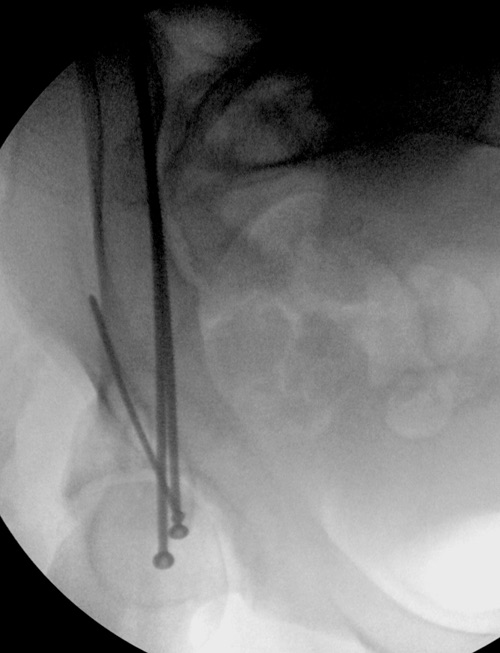

Дискуссия показывает интересные стороны развития тактики лечения переломов вертлужной впадины. Для разработки лечебной тактики сперва надо установить диагноз, и разбор показывает, что не все справляются с такой задачей! Изучение перелома надо начать из стандартных снимков: для переломов костей таза: прямой, inlet и outlet, а для перелома вертлужной впадины - снимки по Judet.

В последнее время, из-за красоты участился показ 3D снимков, хотя надо начать c обычных, и, по необходимости, компьютерная томография с 3D! Без головки бедра 3D покажет общую картину и вовлечение сустава, а более детально только в срезах КТ.

Данная картина показывает очень редкий перелом передней колонны, но перед операцией еще раз надо просмотреть обещанные дополнительные КТ срезы.

“я и подумал о возможности АВФ. Простите мне мою упрямость”

По поводу лечения, мнения разделились между открытой репозицией или не открывать! Нельзя подгонять метод под имеющийся инвентарь! Предложенный метод идеальный для damage control при разрыве тазового кольца! Метод Илизарова, как спасательный круг, когда кроме спиц ничего, но времена изменились, везде доступны современные методы фиксации! Наружный фиксатор обязывает вести наблюдение за спицами. И еще, вряд ли аппарат со множественными спицами в тазу даст возможность мобилизовать больного! Кроме этого, установка “трансфрактурных спиц” тоже не простая задача, чем винты, открытым методом!

Представленные слайды Александром из Севастополя, имеет ценность, но, кроме inlet, остальные стандартные Judet рентген снимки должны показать правоту принятого решения. Возможно, здесь фиксация перелома вертлужной впадины, но по рентгену трудно понять!

Здесь пример перелома передней стенки, где сохранен принцип фиксации передней колонны. Для доступа Smith Petersen с остеотомией ASIS. Мышца сарториус отодвинута, и сделана ре-фиксация на свое место винтами. При хорошем обзоре, наличие Farabeuf или Jungblud forceps облегчит репозицию.